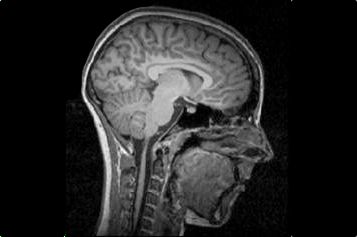

Doch da ist noch eine Folge fürs Gehirn. Eine, die nicht so offensichtlich ist: Während der Körper immer weiter ausmergelt, schrumpft auch das Gehirn. Es kommt zu einer Hirn-Atrophie, wie Mediziner sagen, umgangssprachlich auch „Hirnschwund“ genannt. Vor allem die graue Substanz geht zurück, also die Nervenzellkörper, die unter anderem die Hirnrinde ausmachen. „Dann ist der äußere Liquor-Raum erweitert. Das ist der Bereich zwischen zwei Hirnhäuten, die das Gehirn umgeben“, sagt Ehrlich.

Graue Substanz schrumpft um ein Fünftel

Außergewöhnlich konkrete Zahlen liefert eine Studie, die an der Uniklinik der RWTH Aachen durchgeführt wurde und 2012 erschien. Untersucht wurden 19 magersüchtige Mädchen im Alter zwischen zwölf und 17 Jahren, die gerade in ein Krankenhaus aufgenommen worden waren, um eine stationäre Therapie zu beginnen. In der Kontrollgruppe waren 19 Mädchen, die genauso alt waren, einen ähnlichen Intelligenzquotienten hatten, aber nicht essgestört waren. Das Gesamt-Hirnvolumen an sich – also die Menge an grauer Substanz, weißer Substanz und Hirnflüssigkeit – unterschied sich nur unwesentlich zwischen den beiden Gruppen. Doch im Detail offenbarte sich: Bei den gesunden Mädchen hatte die graue Substanz ein Volumen von durchschnittlich 739 Kubikzentimetern – bei den magersüchtigen Mädchen hingegen waren es durchschnittlich 605 Kubikzentimeter, also rund 18 Prozent weniger. An Hirnflüssigkeit hatten die gesunden Mädchen durchschnittlich 422 Kubikzentimeter – die magersüchtigen Mädchen hingegen 535 Kubikzentimeter, also gut 27 Prozent mehr. Die weiße Substanz war bei den kranken Mädchen nur ein wenig geringer als bei den gesunden.

Eines muss man jedoch bedenken bei all diesen Zahlen: Es sind immer Durchschnittswerte. Eine Magersüchtige kann durchaus mehr graue Substanz haben als eine gesunde Schulkameradin. Magersucht-Forscher Ehrlich geht davon aus: „Bei den jugendlichen Magersüchtigen ist wohl etwa ein Drittel von einer radiologisch auffallenden Atrophie betroffen.“

Marie wurde gleich für eine stationäre Therapie zu Stefan Ehrlich geschickt. „Hier hat man mich in eine Röhre gelegt, um Bilder von meinem Kopf aufnehmen zu können. Aber ich habe lieber nicht nachgefragt, was dabei herausgekommen ist“, sagt die Siebtklässlerin. „Ich war so schon völlig fertig.“ Maries Magnetresonanztomographie (MRT) wurde Ehrlich zufolge aber nicht durchgeführt, um zu schauen, ob ihr Hirn geschrumpft war. „Das MRT war zu Forschungszwecken. Ein klinisches MRT ist nur nötig, wenn organische Ursachen wie ein Hirntumor ausgeschlossen werden sollen. Die kognitiven Einbußen kommen manchmal auch ohne eine deutliche Atrophie vor.“